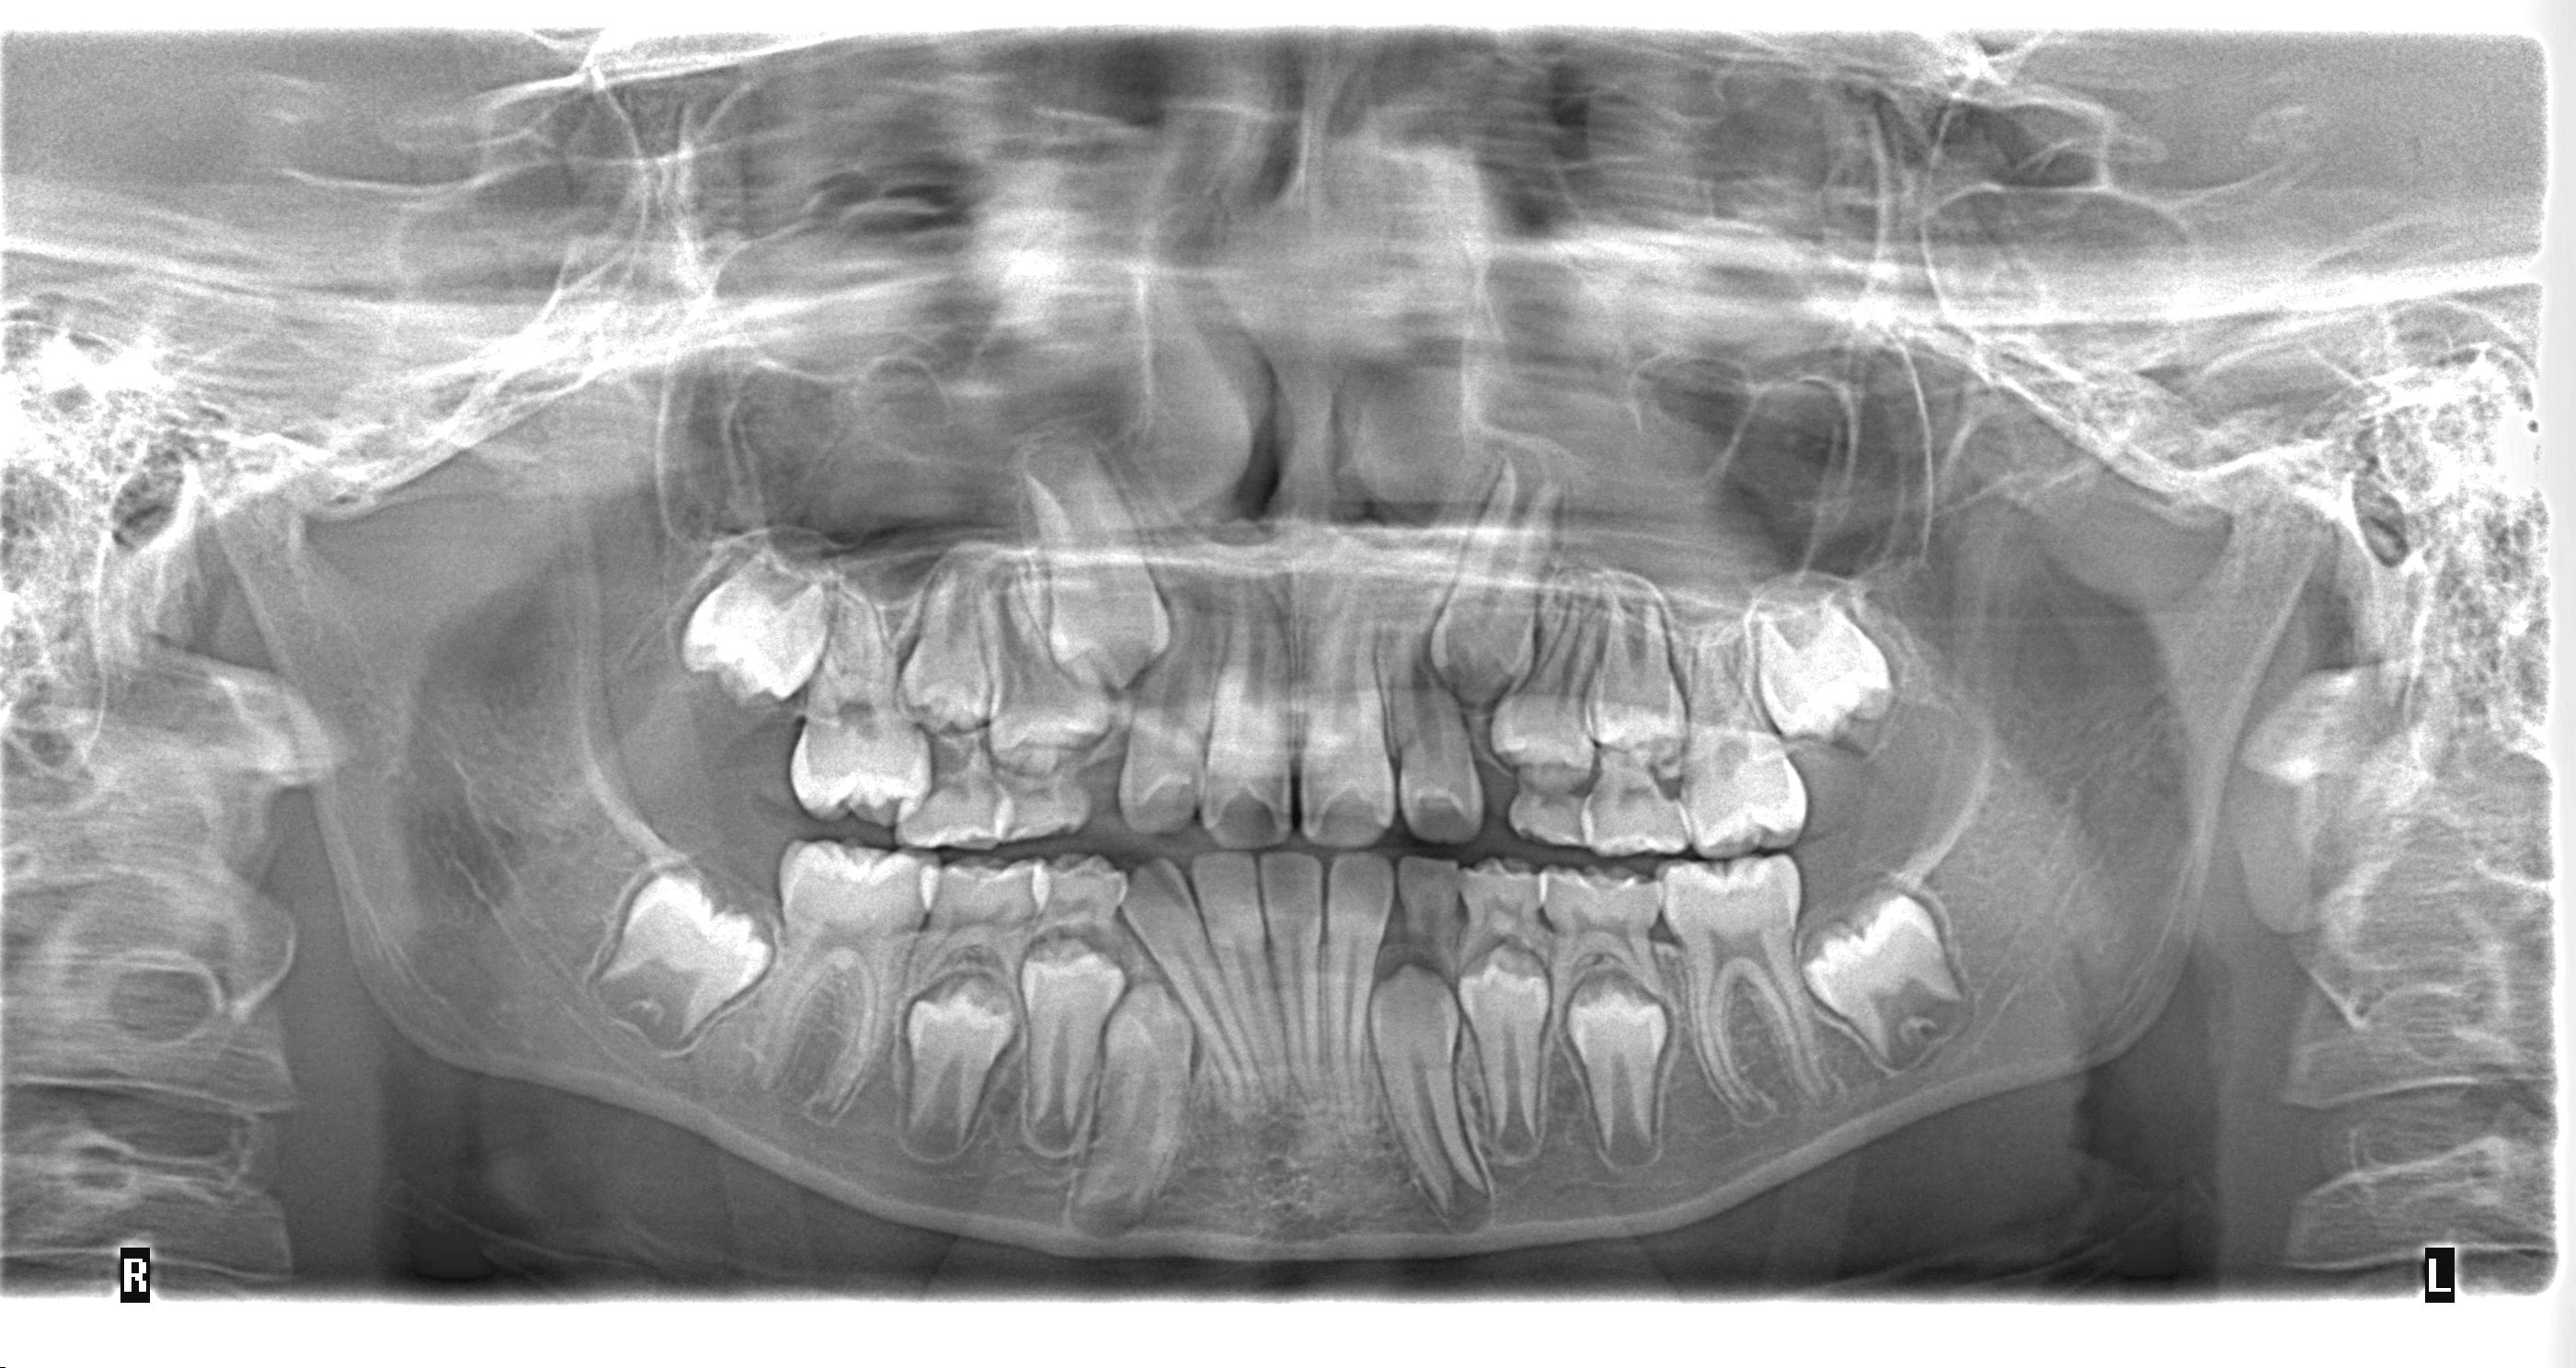

panoramica digital